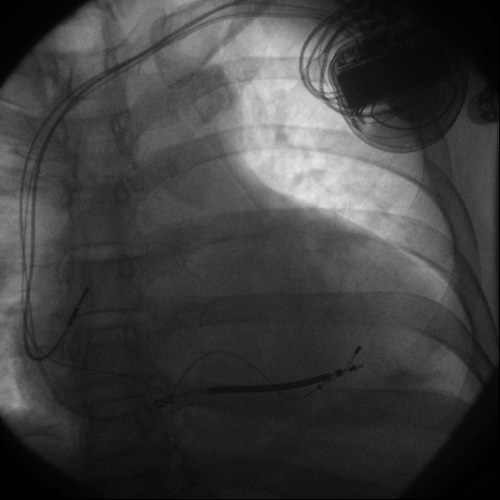

本例患者,男性,59歲,診斷:慢性心力衰竭、擴(kuò)張型心肌病、心功能IV級(jí)、心律失常、頻發(fā)室性早搏 。自2011年以來(lái),反復(fù)因活動(dòng)后胸悶、氣短、呼吸困難,下肢水腫于我院多次住院,心衰癥狀不斷加重。本次入院后,經(jīng)心內(nèi)二科張曉鋒主任、呂強(qiáng)副主任醫(yī)師認(rèn)真研究、仔細(xì)分析,明確患者病情,在超聲科黃曉欣主任和謝云副主任親自操作,反復(fù)檢查心臟組織多普勒,確定該患者有很好的CRTD適應(yīng)證,預(yù)計(jì)會(huì)有較好的療效。在充分與患者及家屬溝通,并在醫(yī)保辦主任焦迎春、副主任陳冬娥大力宣傳銅川醫(yī)保政策配合下,患者及家屬同意采用CRTD治療,為確保心內(nèi)二科首例CRTD的成功,特意邀請(qǐng)西京醫(yī)院沈敏教授幫助指導(dǎo),導(dǎo)管室邵玉玲主管護(hù)師、車(chē)曉偉技師通力合作,美敦力公司也給予了大力支持,專(zhuān)程從青島委派3名高級(jí)技術(shù)人員,在手術(shù)現(xiàn)場(chǎng)程控,提供器械/器材技術(shù)支持。手術(shù)在經(jīng)歷兩個(gè)小時(shí)的緊張而有條不紊的操作后,順利完成。術(shù)后經(jīng)過(guò)精心治療,手術(shù)傷口痊愈拆線,起搏器工作狀態(tài)正常,患者恢復(fù)良好,心臟功能及癥狀較手術(shù)前顯著改善,遠(yuǎn)期療效在進(jìn)一步觀察中,并將通過(guò)不斷程控,優(yōu)化心臟起搏器起搏參數(shù),達(dá)到更好的治療效果。

該手術(shù)屬于操作復(fù)雜、手術(shù)難度較大的一類(lèi)手術(shù),該手術(shù)技術(shù)結(jié)合了冠狀動(dòng)脈介入操作技術(shù)、心臟電生理檢查、治療操作技術(shù)及起搏器操作等復(fù)雜的操作技術(shù),且在冠狀竇靜脈血管內(nèi)操作,因血管壁較薄弱,無(wú)肌肉層,且有靜脈瓣阻擋,增大了手術(shù)操作的風(fēng)險(xiǎn)。西安高新醫(yī)院心內(nèi)二科的首例首例CRTD的成功完成為該項(xiàng)技術(shù)的進(jìn)一步開(kāi)展摸索了經(jīng)驗(yàn),相信這項(xiàng)技術(shù)的廣泛開(kāi)展,在取得一定的經(jīng)濟(jì)效益的同時(shí),會(huì)給廣大患者帶來(lái)更大的福音,將拓展醫(yī)院慢性心力衰竭的治療方法,提高西安高新醫(yī)院的影響力。